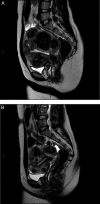

Uterine fibroids (also known as leiomyomas or myomas) are the most common form of benign uterine tumors. Clinical presentations include abnormal bleeding, pelvic masses, pelvic pain, infertility, bulk symptoms and obstetric complications.Almost a third of women with leiomyomas will request treatment due to symptoms. Current management strategies mainly involve surgical interventions, but the choice of treatment is guided by patient's age and desire to preserve fertility or avoid 'radical' surgery such as hysterectomy. The management of uterine fibroids also depends on the number, size and location of the fibroids. Other surgical and non-surgical approaches include myomectomy by hysteroscopy, myomectomy by laparotomy or laparoscopy, uterine artery embolization and interventions performed under radiologic or ultrasound guidance to induce thermal ablation of the uterine fibroids.There are only a few randomized trials comparing various therapies for fibroids. Further investigations are required as there is a lack of concrete evidence of effectiveness and areas of uncertainty surrounding correct management according to symptoms. The economic impact of uterine fibroid management is significant and it is imperative that new treatments be developed to provide alternatives to surgical intervention.There is growing evidence of the crucial role of progesterone pathways in the pathophysiology of uterine fibroids due to the use of selective progesterone receptor modulators (SPRMs) such as ulipristal acetate (UPA). The efficacy of long-term intermittent use of UPA was recently demonstrated by randomized controlled studies.The need for alternatives to surgical intervention is very real, especially for women seeking to preserve their fertility. These options now exist, with SPRMs which are proven to treat fibroid symptoms effectively. Gynecologists now have new tools in their armamentarium, opening up novel strategies for the management of uterine fibroids.